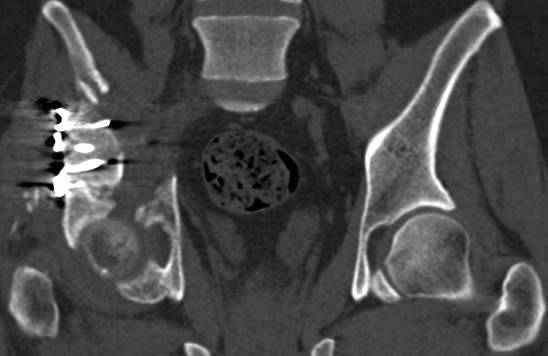

>Вопрос к знатокам: Так что это?

высылаю дополнительно сканы.

итак, второй вариант: высокий двухколонный с вовлечением КПС... Ни одно из основных повреждений не репонировано, кроме задней стенки. Скорее всего попытка реконструкции вертлуги сейчас будет очень травматичной и не очень эфективной, т.е. вероятный риск более значим, чем ожидаемая польза... Лучше подождать, и потом сразу эндопротез

подождать сколько, чего? такая дыра в задней колонне не закроется никогда.

потом эндопротез какой? в такой ситуации приходит на ум Burch-Schneider cage, в 35 лет, дальше что делать?